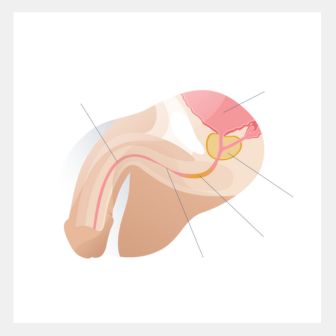

RECONSTRUCTIVE UROSUREGRIES

Professional medical services